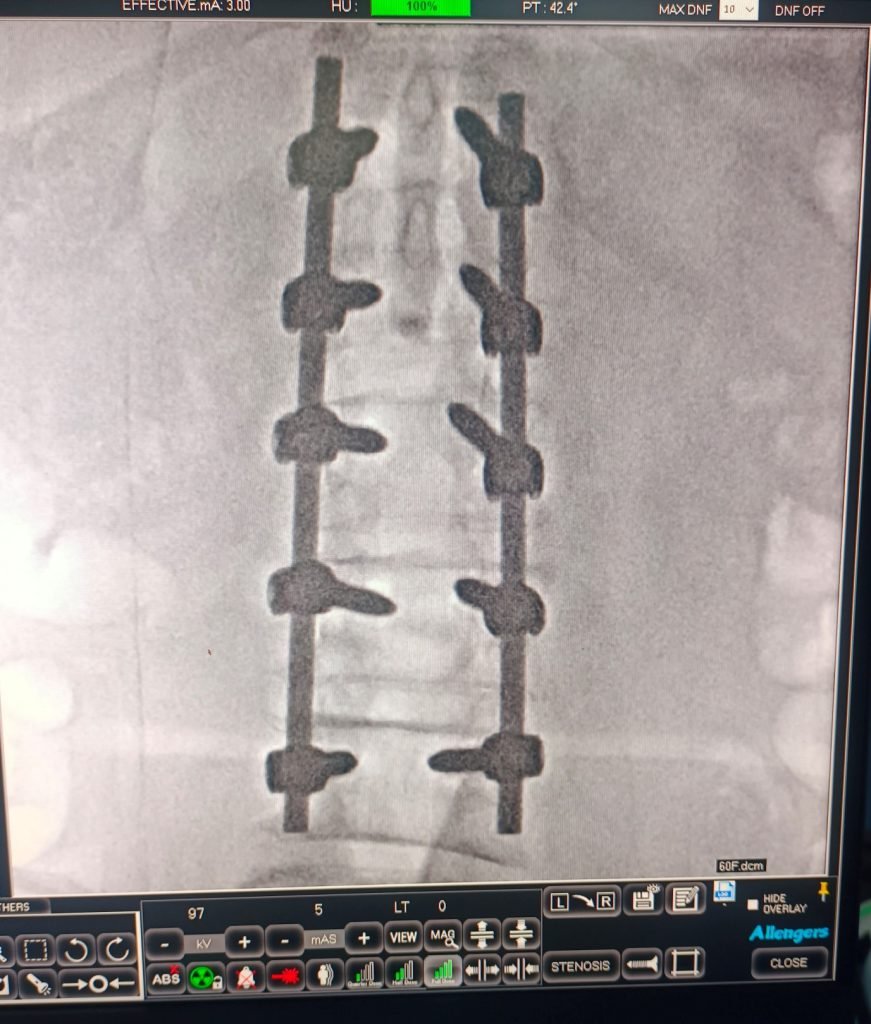

Treatment:

Correction of spinal curvature using titanium screws and rods to restore alignment and provide stabilization.